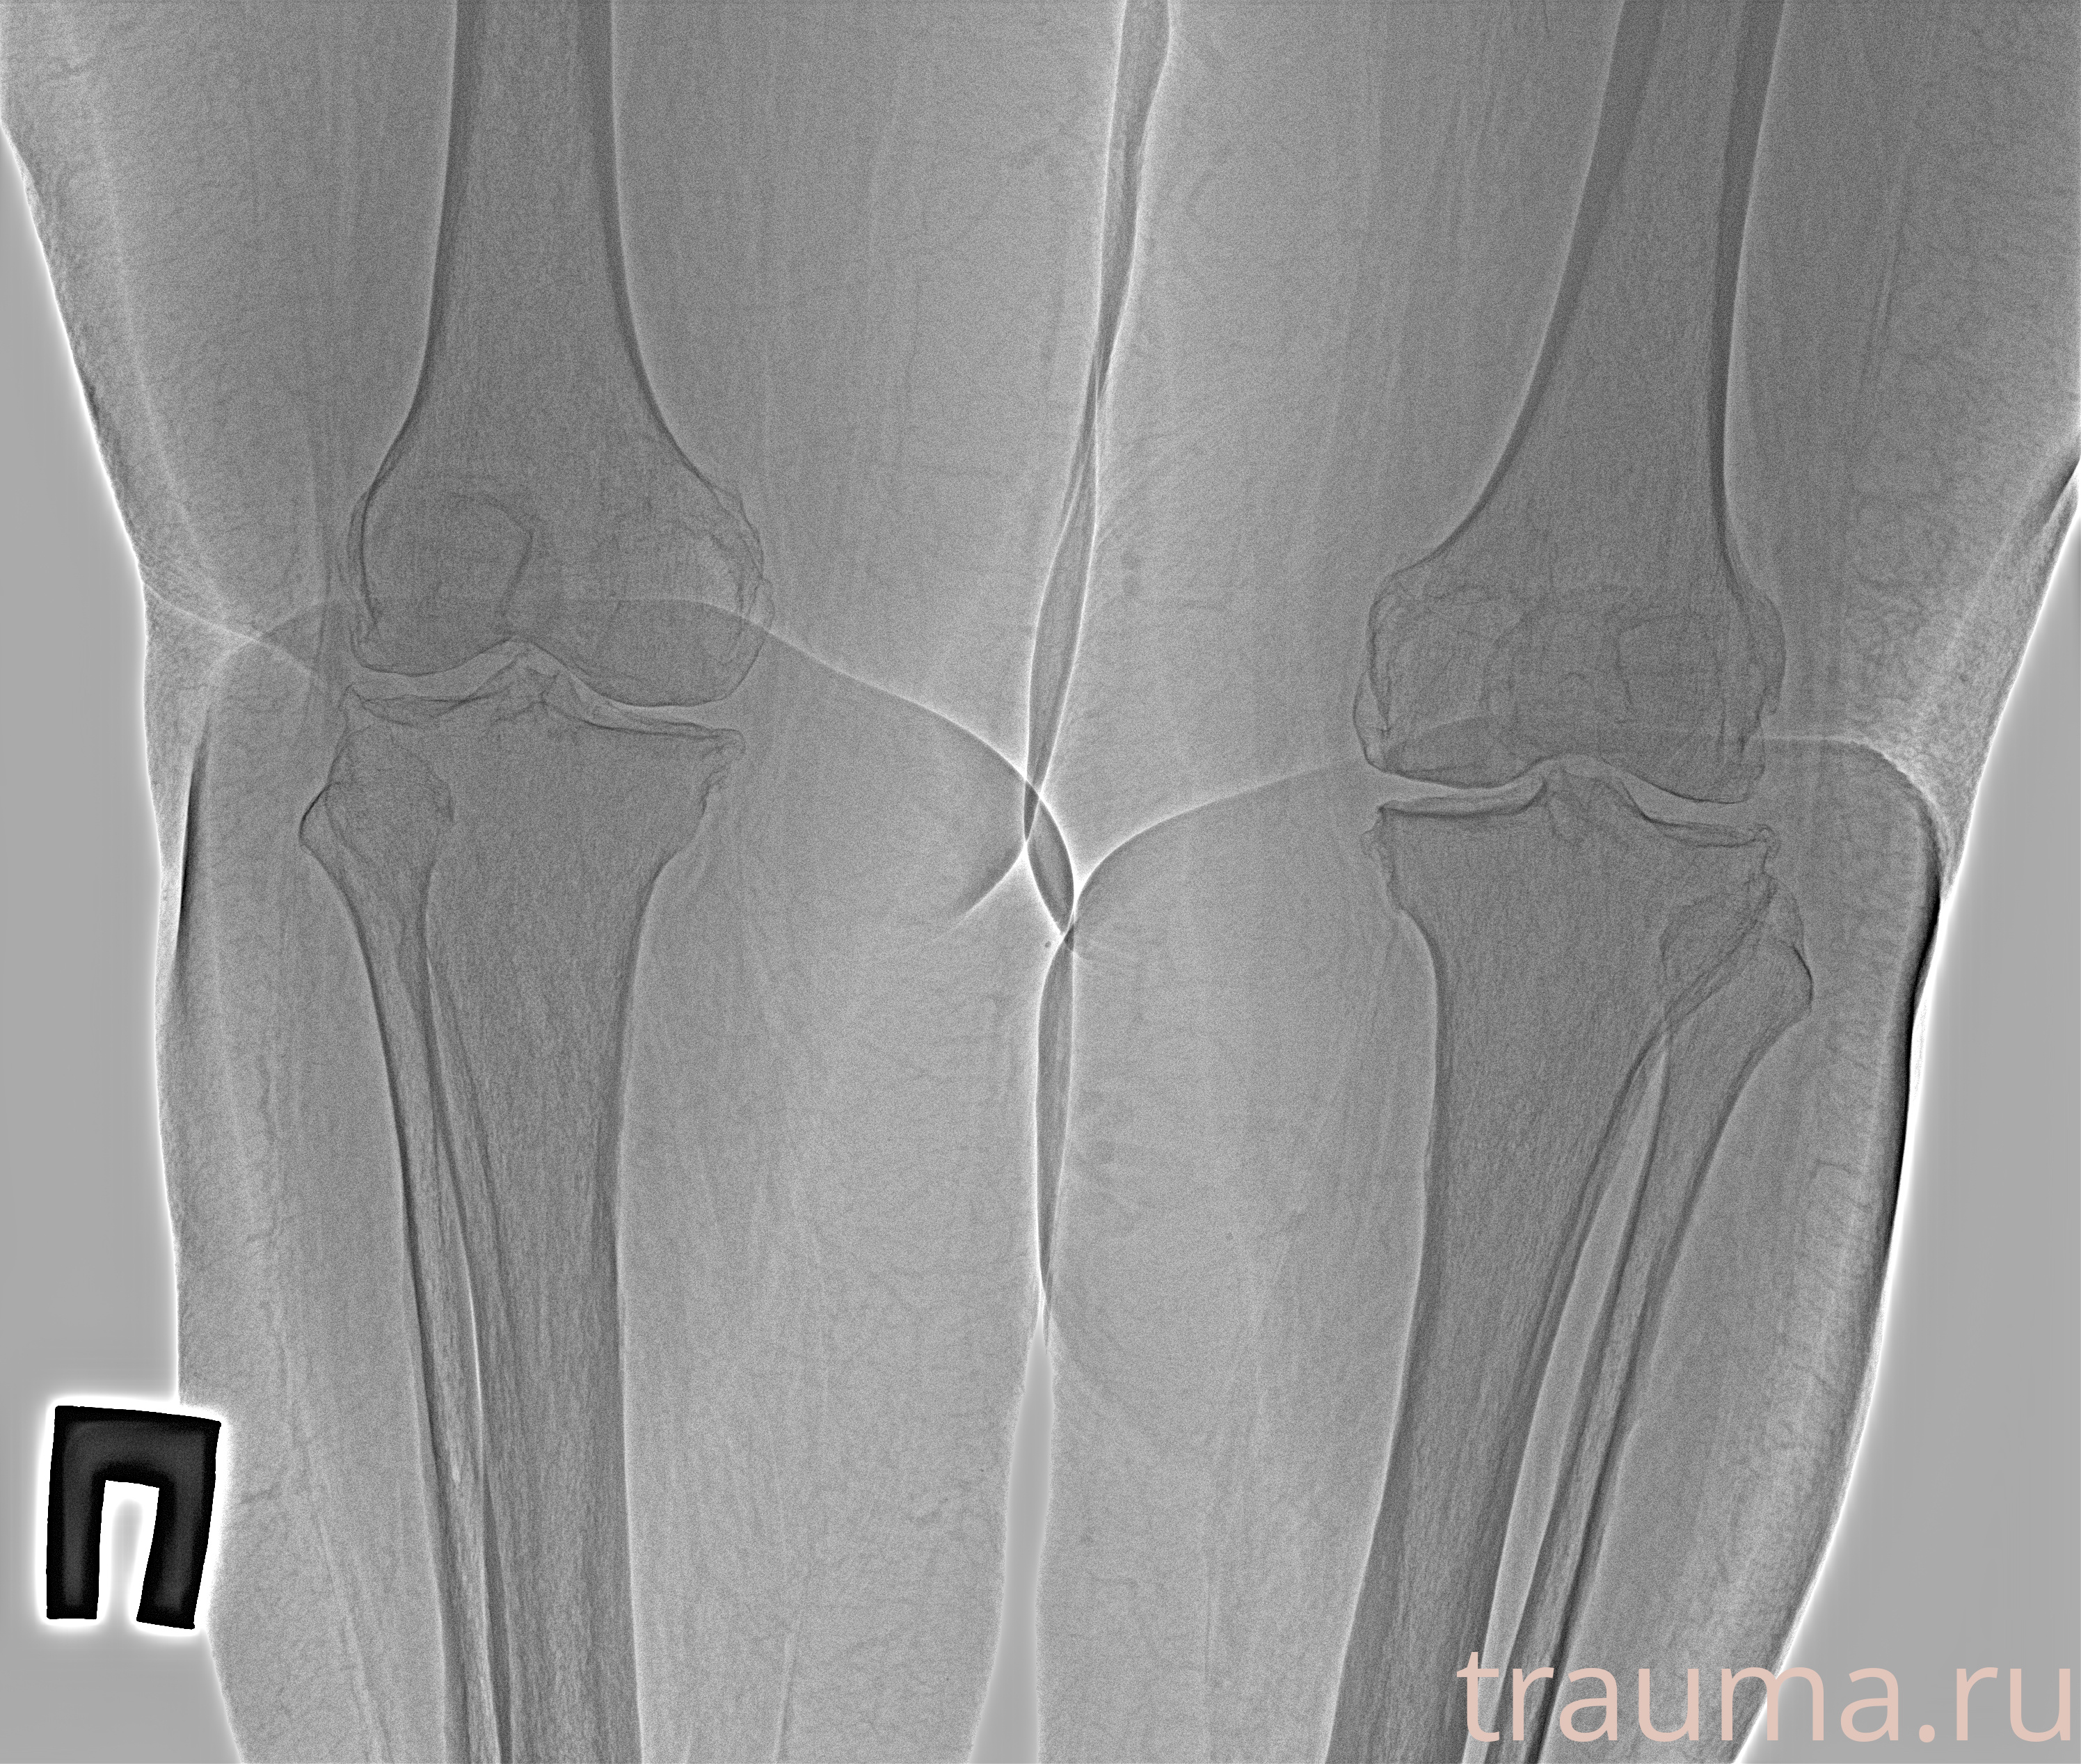

Рентген на дому: по вашему адресу приезжает врач-рентгенолог, травматолог-ортопед с мобильным рентгеновским аппаратом, проводит диагностику травмы или заболевания, делает необходимые рентгенограммы, дает рекомендации по дальнейшему лечению. Получить качественные снимки в домашних условиях возможно благодаря уникальной методике, разработанной МосРентген Центром для института  Склифосовского